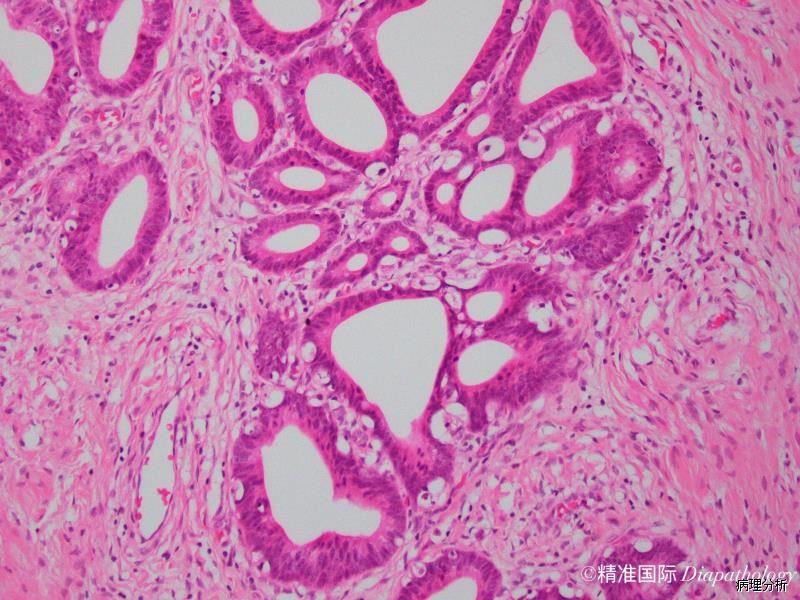

宫颈腺癌,普通型

Endocervical Adenocarcinoma, Usual Type

为最常见宫颈腺癌类型,黏液分泌相对减少。

圆形、椭圆形腺体,伴筛状及乳头状结构;

微腺体增生样;

微囊性;

腺、囊内可充满黏液,也可无黏液;

假复层排列;

核增大,长形,深染,核仁突出;

胞浆嗜双色性或嗜酸性;

可见凋亡细胞。

间质

可有黏液或黏液湖形成;

可见促结缔组织增生反应。